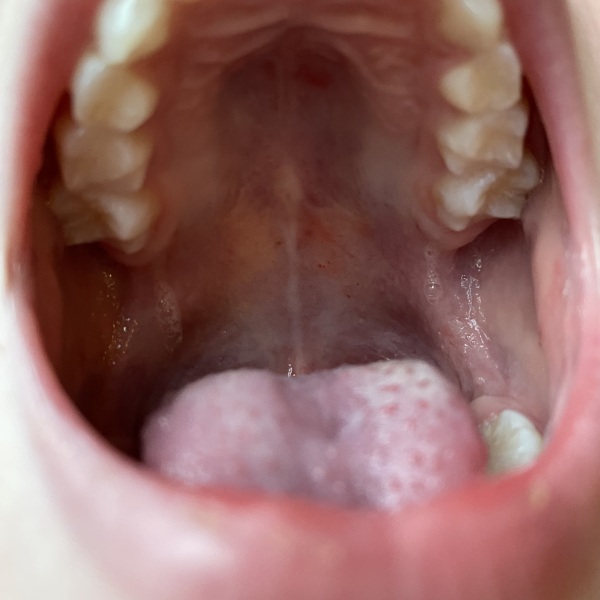

symptoms - summer period had red rash on face (not over nose) that would come out with sun and if poorly but disappear within an hour, intermittent non blanching Petachie rash on body that would coincide with red face rash flare, long periods of intermittent low grade fever, intermittent joint pain and pins and needles, very pale, low iron (but does have restricted diet), intermittent itchy skin, during an infection she often gets a prickly heat looking rash all over her body, frequent Petachie spots inside mouth, now it’s cooler she has almost daily mottled skin which is really bad on legs particularly when she is poorly even if house is warm, intermittent blue lips and blue nails, bloods taken at hospital three times this year were all clear, urine test in Aug was clear, oxygen levels fine after last episode of blue lips.